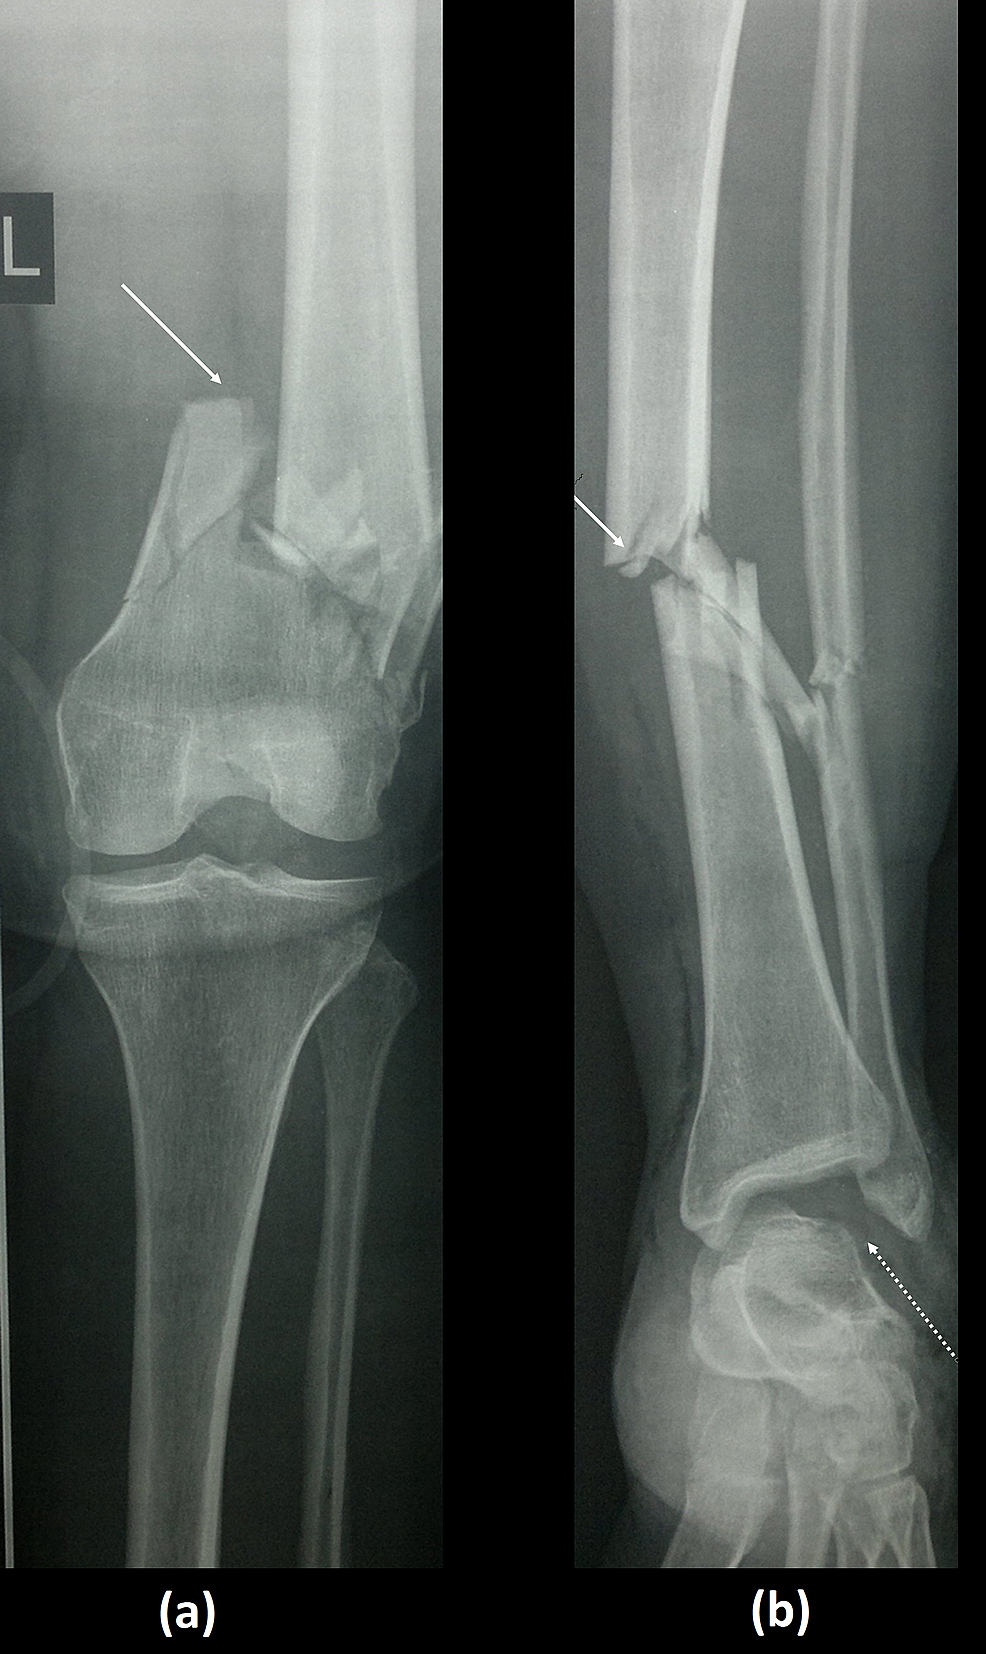

Case 9, type IIc floating knee with (A) closed fractures of the left Floating Knees floating knee is a flail knee joint resulting from fractures of the shafts or adjacent metaphyses of the femur and ipsilateral tibia (see image below). floating knee, referred to as ipsilateral fractures of the femur and tibia, is usually. floating knee refers to the knee joint and not necessarily the connection to either long bone. in. Floating Knees.